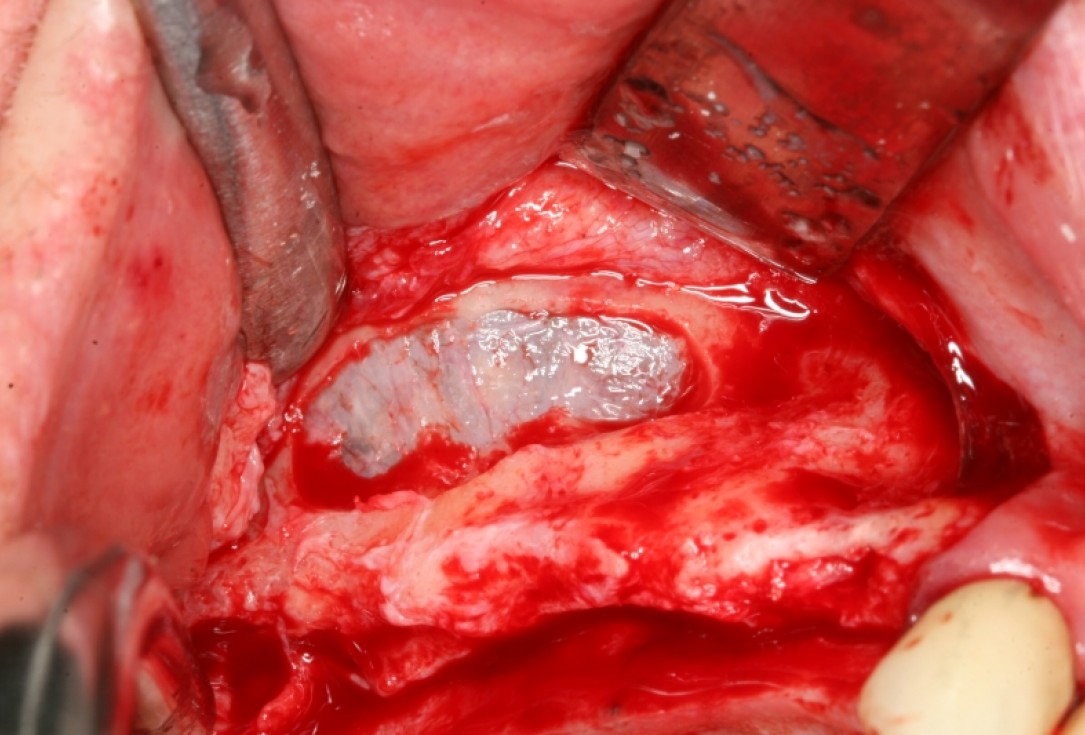

Initial clinical situation with gum recession and labial bone loss eight weeks following tooth extraction